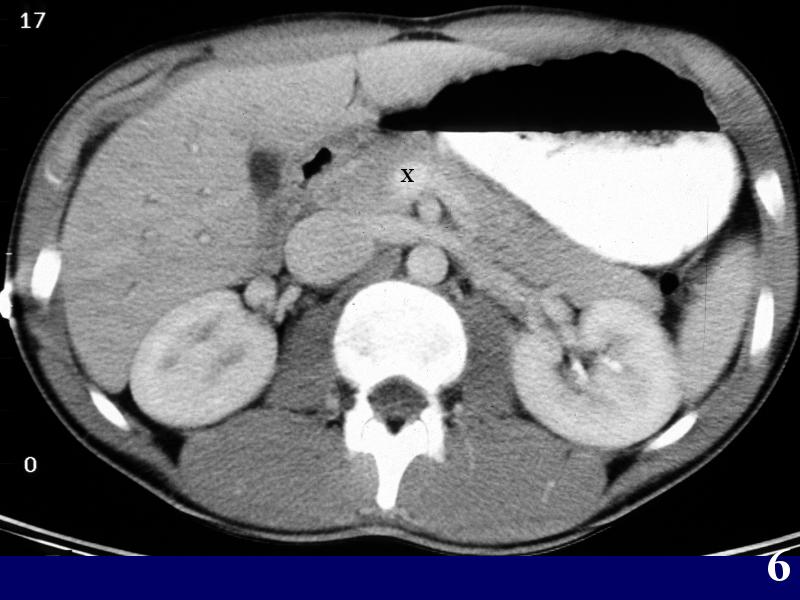

MS 190 CT 17